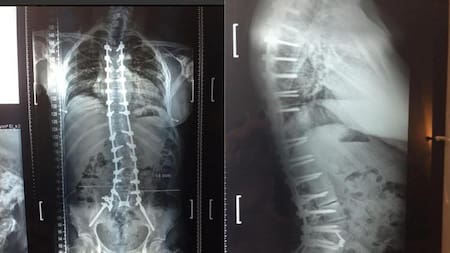

Radiografías practicadas a Ricardo Fort.

En abril de ese año fue operado de esa maldita rodilla: "Fue doloroso, la verdad. Gracias a los calmantes puedo aguantar el dolor y mañana empezaremos con la kinesiología para empezar a mover la pierna y caminar de a poco con muletas", contaría Fort.

La última operación a la que se sometió fue en septiembre: le implantaron 16 tornillos de titanio en la columna, más dos varillas para apuntalarla, y anillos de metal para separar las vértebras y evitar el desgaste de los discos. Aquella cirugía llevó nueve horas, y aunque todo salió bien los problemas no tardaron en llegar luego de que su organismo rechazara los cuerpos extraños, ocasionándole aún más problemas.